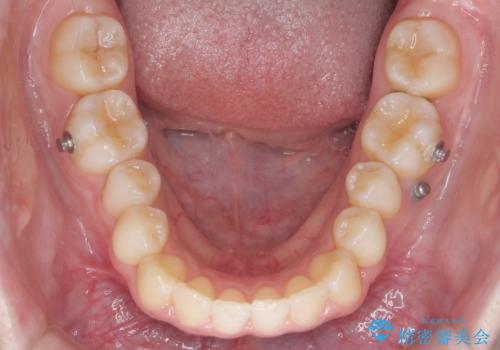

- 矯正装置

- ワイヤー矯正

後ろに下げるために、ワイヤー矯正の前にカリエールという装置を使用しました。